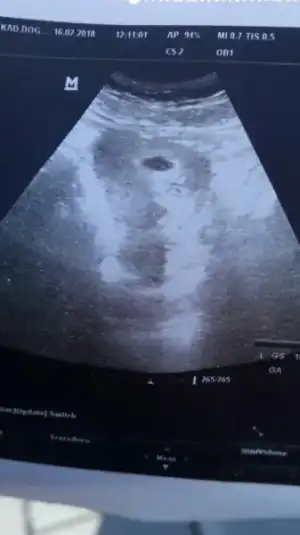

Ultrason görüntüsü böyle 15 mm kese içinde bişey var gibi değil mi anlayan Arkadaslar yorumlarsanız sevinirim 3. Gebeliğin 2 düşüğüm var cok endiseliyim

Canim cok endiselenme.Benim 16 mm kesede 2mm bebek vardi.Cok kucuk sonucta.Doktor bir sey demedi mi?

Devlet e gittm hemen ultrasonu koydu karnıma bastırmadı bile oluşmamış kalp atışı yok cok erken kalk dedi bu kadar biraz inceledim de sağ altta bebiş var gibi inşallah öyledir bakar MSN sende

Var bence de.Zaten net gorebilmek icin doktorun yakinlastimasi gerek.Detayli bakmamis, dert etme 1 hafta sonra rahat gorunur.Cok kafana takildiysa, imkanin varsa ozele git canim.